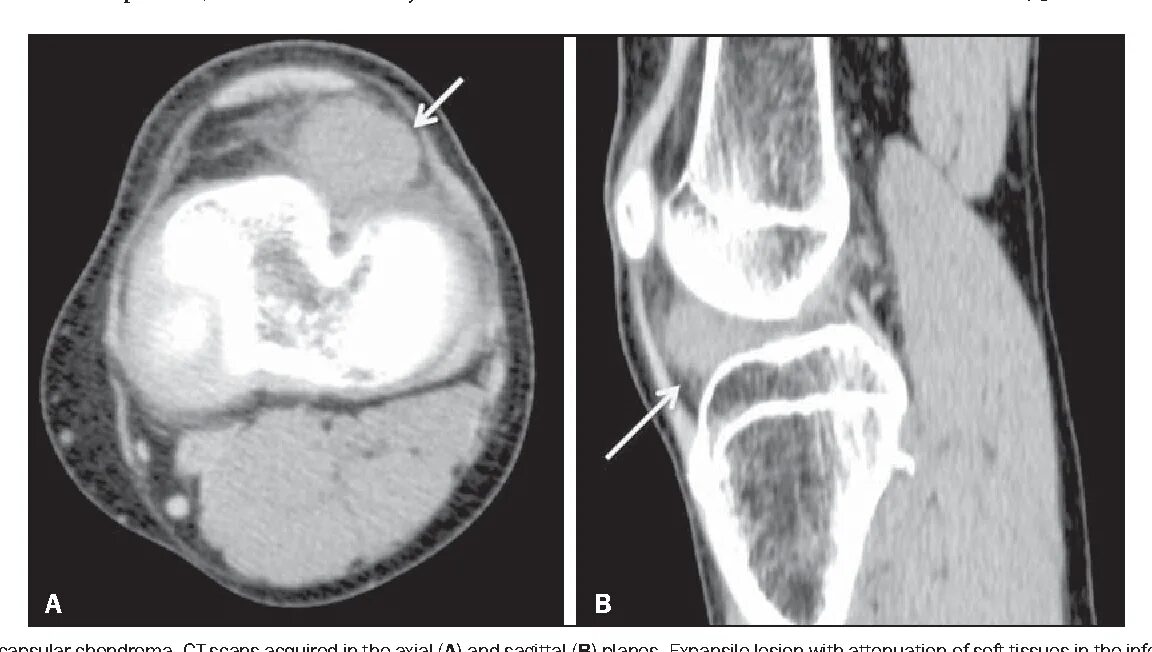

Кт суставов что показывает